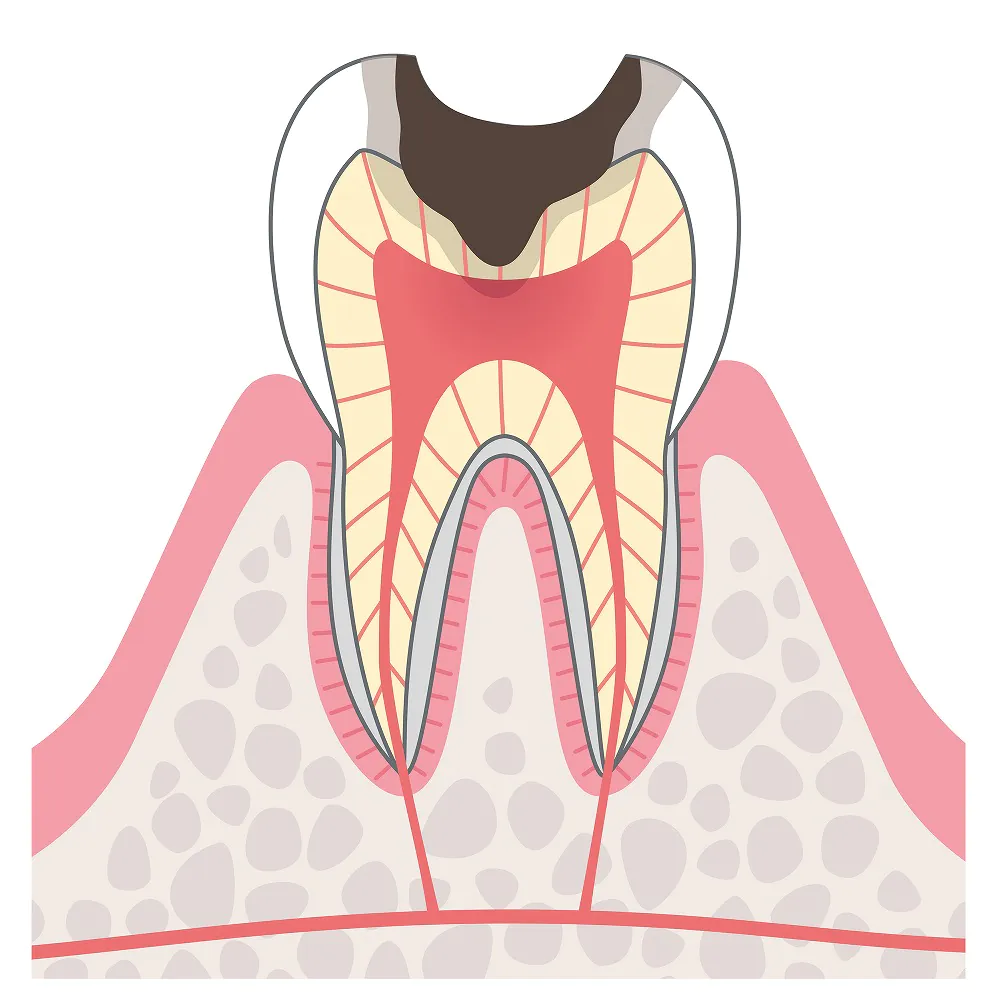

C3:激しい痛みが生じるむし歯

むし歯が歯の神経に達した状態です。強い炎症が起きて激しい痛みが生じるため、この段階で歯医者に駆け込む方が少なくありません。

むし歯が歯の神経に達した状態です。強い炎症が起きて激しい痛みが生じるため、この段階で歯医者に駆け込む方が少なくありません。

治療法

歯の神経が入っている根管という管にアプローチする根管治療を行います。根管内をきれいにして薬を詰め、歯質を被せ物で補います。